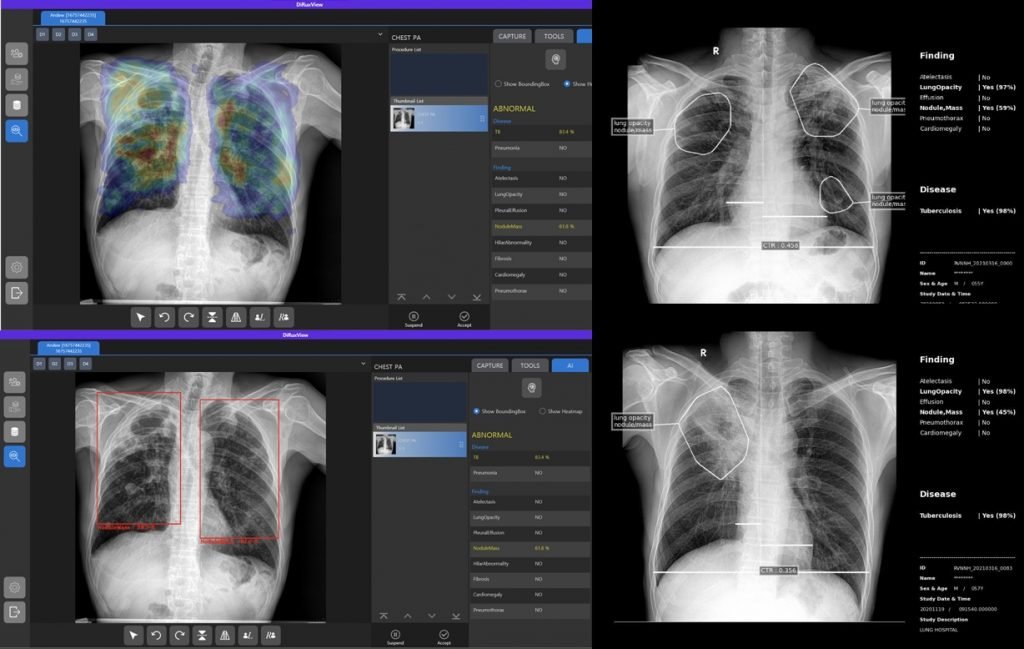

Ai Radiologist Assistant Detection

- Chest Abnormalities: Atelectasis, Lung Opacity, Effusion, Mass, Pneumothorax, Cardiomegaly, Tuberculosis, Nodule

- Diseases: Tuberculosis, Pneumonia

- Lesions: Contour Plot, Heat map, Bounding Box

- Others: Cardiothoraxic Ratio